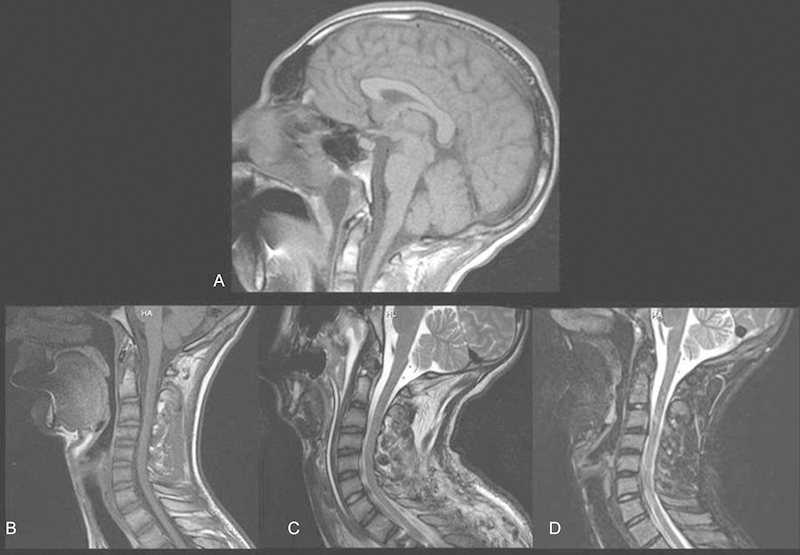

研究设计案例报告。临床目的是报道导丝辅助椎弓根螺钉置入与喉返神经(RLN)神经失用症之间先前未知的关联,以及这种关联如何与Tapia综合征的症状重叠;我们还报告了我们对该患者的临床管理方法。方法1例17岁男性特发性脊柱侧凸患者经后路内固定及T1-L1关节融合术后出现Tapia综合征。拔管后,患者声音沙哑,吞咽困难。影像学显示T1前体皮层与右侧RLN相对应的裂口。结果耳鼻喉科检查发现右声带不动,喉内感觉减弱,软喉镜下分泌物淤积提示右侧颅神经X损伤,左侧舌偏。在病人被送回家之前,在改良的钡吞咽过程中误吸促使插入经皮内窥镜胃造口管。术后第20天,钡剂吞咽显示误吸减少,患者报告症状完全缓解。取下饲管,1个月后恢复正常饮食。Tapia综合征,或持续性单侧喉部和舌下麻痹,是一种罕见的神经失用症,以前未观察到其与T1沿RLN路径的椎体破裂有关。结论Tapia综合征在术后症状持续时应作为鉴别诊断的考虑因素,脊柱外科医生应意识到这是脊柱内固定导丝的潜在并发症。

Study Design Case report. Clinical Question The clinical aim is to report on a previously unknown association between guidewire-assisted pedicle screw insertion and neuropraxia of the recurrent laryngeal nerve (RLN), and how this may overlap with the signs of Tapia syndrome; we also report our approach to the clinical management of this patient. Methods A 17-year-old male patient with idiopathic scoliosis experienced Tapia syndrome after posterior instrumentation and arthrodesis at the level of T1-L1. After extubation, the patient had a hoarse voice and difficulty in swallowing. Imaging showed a breach in the cortex of the anterior body of T1 corresponding to the RLN on the right. Results Otolaryngological examination noted right vocal fold immobility, decreased sensation of the endolarynx, and pooling of secretions on flexible laryngoscopy that indicated right-sided cranial nerve X injury and left-sided tongue deviation. Aspiration during a modified barium swallow prompted insertion of a percutaneous endoscopic gastrostomy tube before the patient was sent home. On postoperative day 20, a barium swallow demonstrated reduced aspiration, and the patient reported complete resolution of symptoms. The feeding tube was removed, and the patient resumed a normal diet 1 month later. Tapia syndrome, or persistent unilateral laryngeal and hypoglossal paralysis, is an uncommon neuropraxia, which has previously not been observed in association with a breached vertebral body at T1 along the course of the RLN. Conclusion Tapia syndrome should be a differential diagnostic consideration whenever these symptoms persist postoperatively and spine surgeons should be aware of this as a potential complication of guidewires in spinal instrumentation.